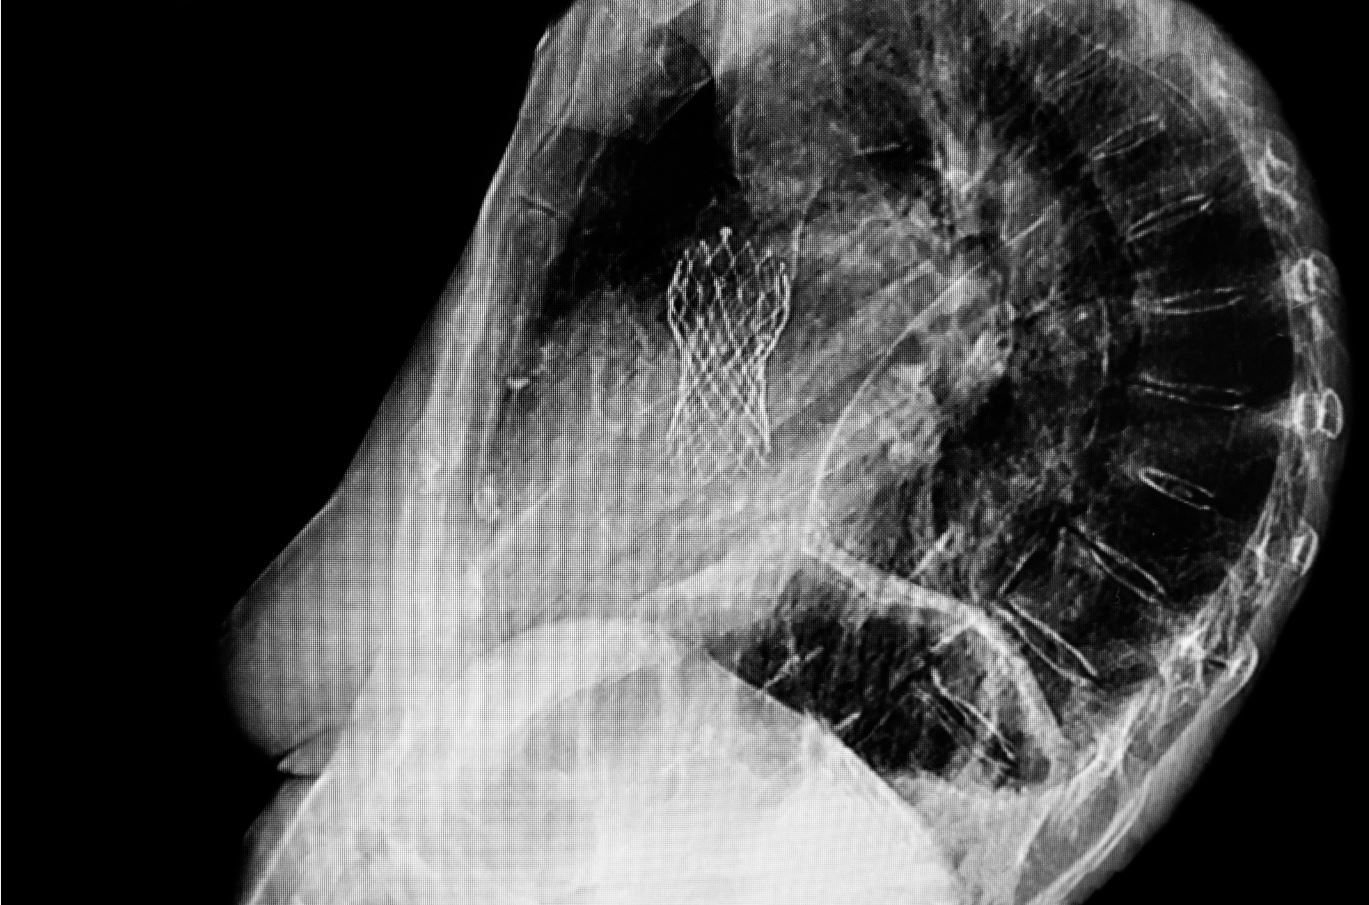

Lateral checst x-ray showing aortic valve replacement done through a femoral artery. ©DOUGLAS/stock.adobe.com)